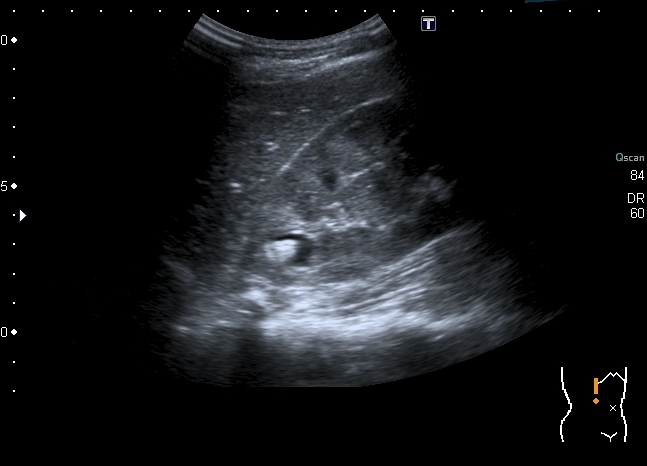

Мальчик 14 лет, на плановой госпитализации, выставлен хронический пиелонефрит.

Ранее на КТ - Киста почки с кальцинатами.

Мальчика выписали без рентгенологического исследования. Будем обходиться УЗИ. Почему это не может быть кистой с конкрементами? Формирование конкрементов в кисте менее вероятно, чем в дивертикуле чашечки или в расширенной чашечке при синроме Фрейли. Но полость уж больно круглая, да и связи с ЧЛС и конфликта с интраренальным сосудом сколько не смотрел, я не увидел.